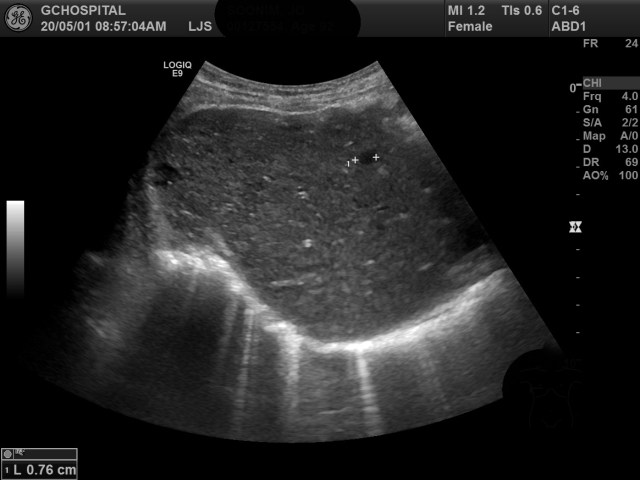

간 내부에는 다수의 크기가 작은 단순낭종들이 함께 발견되었습니다. 위 영상에서 커서로 표시되있는 병변이 그 중 하나이며, 에코가 없는(Anechoic)것을 확인할 수 있지만, 단순낭종을 진단하는데 필요한 중요한 소견인 후방에코강조소견을 확인하지는 못했습니다.